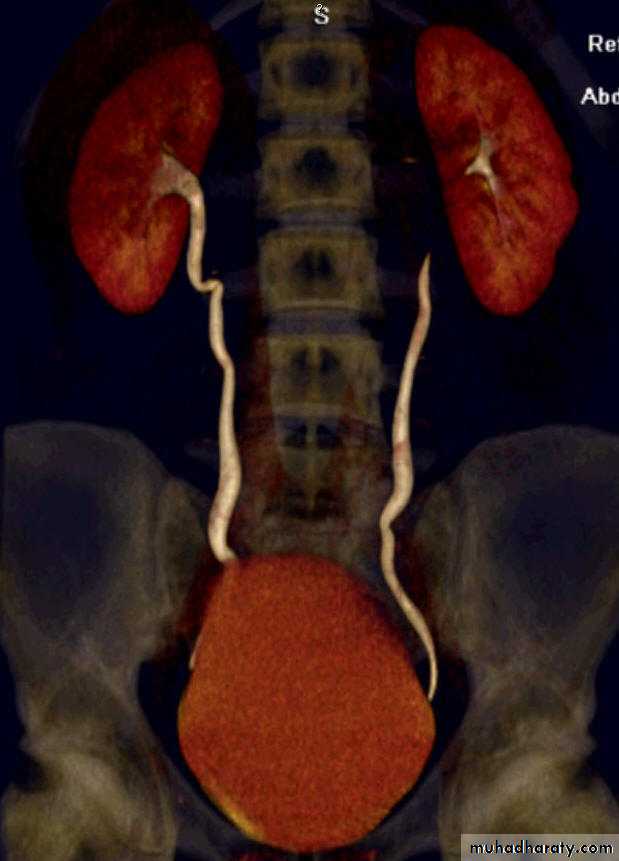

4. Horseshow kidney: fusion of the lower

pole, long axis parallel to the spine, mal-rotationof both kidneys so the pelvis of the kidneys

directed anterior or lateral . Obstruction and

infection are common . Its diagnosis is suggested

by US and confirmed by IVU or CT